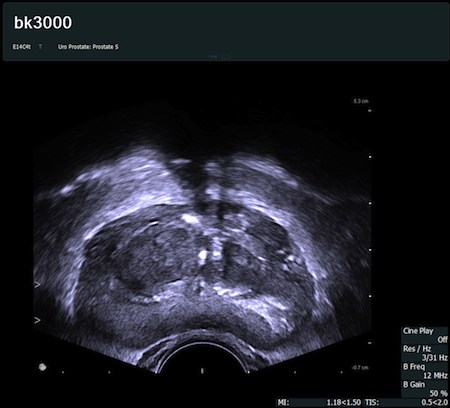

numer 1 na świecie w obrazowaniu prostaty i narządów układu moczowego

opatentowana i najskuteczniejsza metoda wykonywania biopsji prostaty

Obrazy kliniczne uzyskane aparatem bk3000

Fot. Poprzeczny przekrój gruczołu krokowego uzyskany głowicą transrektalną E14C4t.